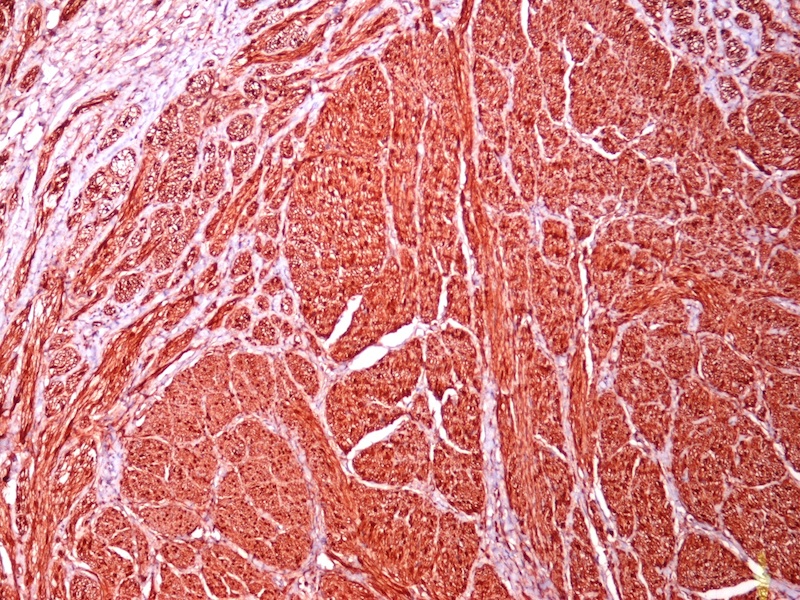

Immunostain images:

Both cases showed disorganized and thickened nerve bundles composed of spindle shaped cells, without atypia. Case A also showed a focal foreign body type giant cell reaction adjacent to the disorganized nerve bundles and a strongly immunoreactive S100 stain.

Histology typically shows hyperplastic nerve bundles, positive for S100.

Immunostain images:

Both cases showed disorganized and thickened nerve bundles composed of spindle shaped cells, without atypia. Case A also showed a focal foreign body type giant cell reaction adjacent to the disorganized nerve bundles and a strongly immunoreactive S100 stain.

Histology typically shows hyperplastic nerve bundles, positive for S100.